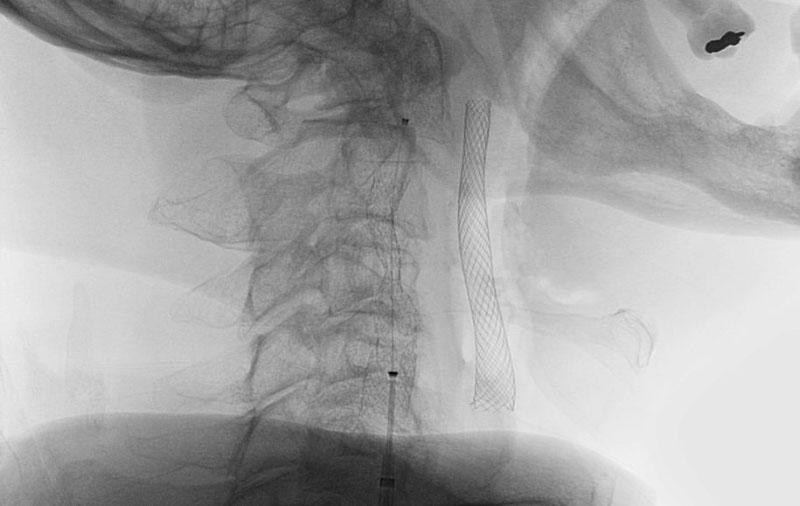

No.1590 手術中

'25年10月

左総頚動脈狭窄症

30代

院内外来